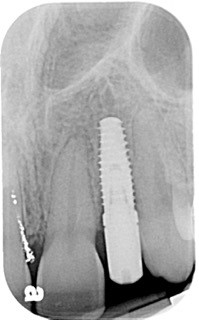

Both Caroline’s and Karen’s lateral incisors were removed, and immediate implants were placed. Although the implant surgeons were different, they were both long-time members of my interdisciplinary team and had significant implant placement experience. Both implants were torqued to 50 Ncm at the time of placement. Provisionals were then placed by me that same day.

Following four months of healing, Karen was appointed in my office for the final restoration of the implant. The provisional was removed, without anesthesia, and the implant impression post was secured to the newly healed implant. The restorative process was uneventful, and a ceramic restoration and gold post were placed.

Another factor is implant design and surface texture. Thread design and pitch may increase the area of implant surface for bone contact. The texture of the implant also plays a role. Textured implants increase surface area for bone cell contact better than machined surfaces.

Lastly, implant diameter and length are significant considerations in implant stability. The longer the implant, the greater the surgeon’s ability to engage bone and achieve primary stability, especially in an immediate extraction — immediate placement scenario. Wider implants provide greater BIC for healing, but implant stability and the emergence profiles of the abutment are limitations for a “wider is better” concept. Ultimately, force management is the key to successful implant integration and longevity!

The failed implant was removed. Following the healing of the site, a second implant was placed. Again, a provisional was placed on the new implant at the time of placement. Maintenance and care instructions were provided. This implant healed uneventfully four months before final restoration. Caroline was delighted with this result.